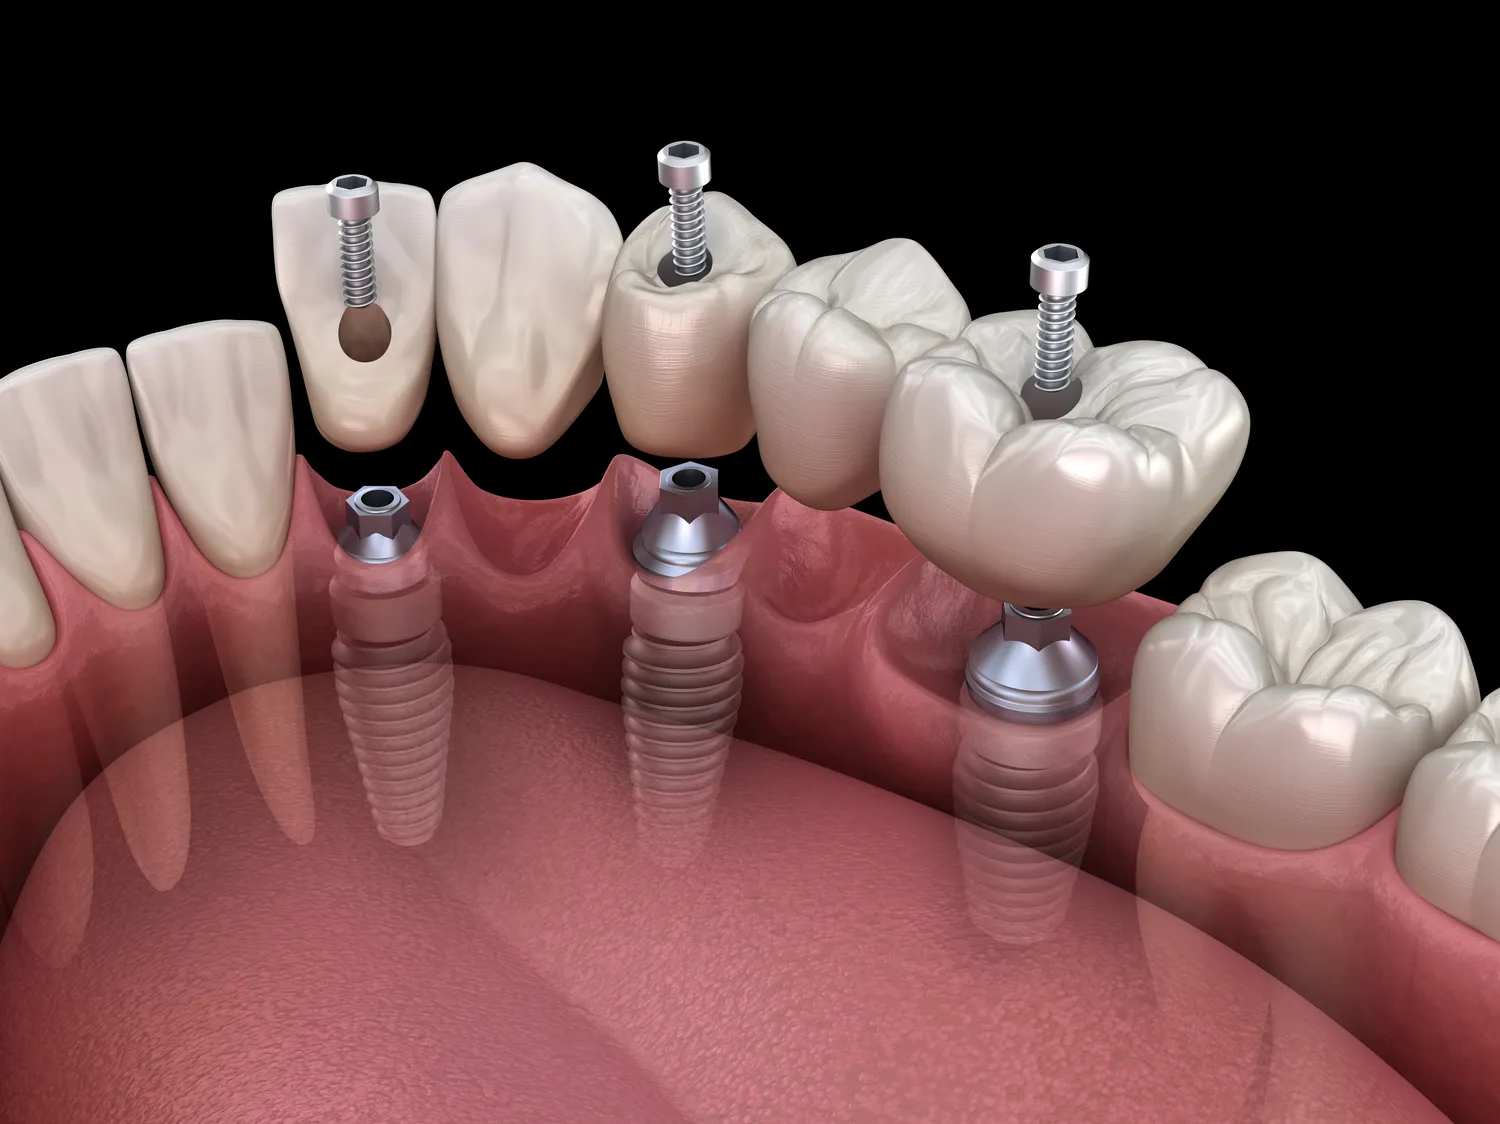

Implanty zębowe to nowoczesne rozwiązanie stosowane w stomatologii, które pozwala na odbudowę brakujących zębów. Istnieje kilka rodzajów implantów, które różnią się materiałem wykonania oraz metodą ich umieszczania. Najczęściej stosowane są implanty tytanowe, które charakteryzują się wysoką biokompatybilnością i trwałością. Tytan jest materiałem, który dobrze integruje się z kością, co sprawia, że implanty te są bardzo stabilne. Innym rodzajem są implanty ceramiczne, które cieszą się rosnącą popularnością ze względu na estetykę oraz mniejsze ryzyko wystąpienia reakcji alergicznych. W zależności od potrzeb pacjenta, lekarz może zaproponować różne rozwiązania, takie jak implanty jednoetapowe czy dwuetapowe. W przypadku implantów jednoetapowych cały proces odbywa się podczas jednej wizyty, natomiast w przypadku dwuetapowych konieczne jest przeprowadzenie dwóch zabiegów.

Proces zakupu i montażu implantów zębowych zaczyna się od konsultacji ze specjalistą, który oceni stan zdrowia jamy ustnej pacjenta oraz przeprowadzi niezbędne badania diagnostyczne. Lekarz może zalecić wykonanie zdjęcia rentgenowskiego lub tomografii komputerowej, aby dokładnie ocenić strukturę kości oraz planować zabieg. Po postawieniu diagnozy i ustaleniu planu leczenia następuje etap przygotowania do zabiegu. W niektórych przypadkach konieczne może być przeprowadzenie dodatkowych procedur, takich jak przeszczep kości czy sinus lift, aby zapewnić odpowiednie warunki do umieszczenia implantu. Sam zabieg polega na wszczepieniu implantu w miejsce brakującego zęba. Po zakończeniu zabiegu pacjent otrzymuje zalecenia dotyczące pielęgnacji oraz diety na czas gojenia. Warto zaznaczyć, że proces integracji implantu z kością trwa zazwyczaj kilka miesięcy, po czym można przystąpić do wykonania korony protetycznej.